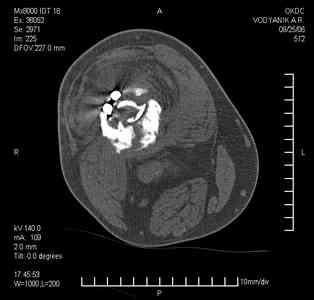

Тугой ложный сустав правого бедра в сочетании неправильно сросшимся переломом большеберцовой кости |

Уважаемые коллеги,В ортопедическое отделение обратился пациент: мужчина 47 лет, который в течение 4-х лет дваждыполучил травму костей, образующих правый коленный сустав. В 2002 v внутрисуставной оскольчатыйперелом проксимального метаэпифиза правой большеберцовой кости; в 2005 v внутрисуставнойоскольчатый перелом дистального метаэпифиза правой бедренной кости. В обоих случаях в разных лечебных учреждениях проводилось оперативное лечение переломов.При осмотре в отделении на основании результатов клинического осмотра и данных визуальныхметодов обследования поставлен диагноз:тугой ложный сустав дистальной трети правой бедренной кости, состояние после накостногоостеосинтеза перелома типа 33-В2.2 ; несросшийся перелом надколенника; неправильно сросшийсяперелом латерального мыщелка правой большеберцовой кости, состояние после металлоостеосинтезаперелома 41-В2.2; сочетанная осевая деформация правой ноги: варусная деформация правого бедра,вальгусная деформация правой голени; посттравматический артроз коленного сустава 4 ст по Kellgren-Lowrence; выраженное нарушение функции ходьбы и опоры. Внешний вид ноги больного, данные рентгенографического обследования и избирательно выделенные компьютерные томограммы приведены в приложении. В именах КТ использовано кодирование уровня по АО, т.е. _41, например, означает проксимальную треть голени.В отделении намечен v очень предварительно v следующий план лечения: 1. Иметь ввиду перспективу тотального эндопротезирования коленного сустава. 2. С учетом п.1 при проведении действий, направленных на устранение ложного сустава бедренной кости не использовать материалы, не подвергающиеся трансформации. 3. В ходе операции, направленной на устранение ложного сустава: А. удалить все металлоконструкции; Б. ревизовать зону пролежня под пластиной на бедре, при наличии признаков достаточной жизнеспособности кости выполнить остеопериостальную декортикацию, дрилинг ложа пластины; В. Удалить рубцовую ткань по плоскости ложного сустава, и в пространстве между костными форагментами, насечь обращенные друг к другу поверхности. Ввести штифт с блокированием (например Stryker с учетом особенностей расположения дистальных блокирующих винтов у этойконструкции). Осуществить остеосинтез с учтанением варусной деформации бедренной кости. Пространство в зоне ложного сустава и пустоты в метафизе бедренной кости заполнить резорбирующимся цементом на основе гидроксиапатита кальция. Для дистальной фиксации использовать винты с переменным шагом резьбы. Вариант:, винты вводить после заполнения метафиза цементом. Дополнительные виды создания межфрагментарной компрессии во встречно-боковом направлении обсуждаются. Г. Быть готовым к кровопотере. Д. Учесть высокий риск инфекции, тромбоэмболических осложнений. Е. Вопрос о внешней иммобилизации решить по результатам оценки стабильности остеосинтеза. Вариант - одноосевой стержневой аппарат для шунтирования гвоздя с модулем на голени и дистракцией коленного сустава в течение 3-5 недель. Просим вашей критики намеченного плана и конструктивных предложений. С уважением к сообществу, Ординатор В.С. Саплин

Движения приличные, есть за что бороться. Такая ротация голени кнаружи, если она действительно есть (для уточнения можно сделать КТ на уровне обоих метафизов и бедреных, и берцовых ксотей, не меняя положение ног во время съемки), большого значения не имеет. А уж на фоне всего остального тут - вообще говорить не о чем.